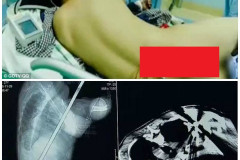

Дочь Брюса Уиллиса: крепкий орешек с волосатыми подмышками... и грудью СМИ сообщили о желании Ким Кардашьян развестись с Канье Уэстом 15 самых сексуальных двойняшек, тройняшек и прочих близнецов со всего мира Миссия провалена или что-то пошло не так Все-таки ты, Кейт? Новые доказательства того, что Питт увлекся именно Хадсон Санта Димопулос поправилась к зиме, чтобы было теплее (Фото) Как безнадежная жертва анорексии смогла победить болезнь Голубая лагуна: стройный как кипарис Рики Мартин отдыхает на пляже с молодым воз... Новый тренд — красный макияж глаз. Советы стилистов (Фото) «Дикий Ангел», «Клон», «Санта-Барбара»: что стало с героями любимых сериалов СЕМИКЛАССНИЦА ИЗ КРАСНОДАРА МАРИЯ СВОИМИ ГОЛЫМИ ФОТО ШОКИРОВАЛА ОДНОКЛАССНИКОВ И... 12 самых добрых поступков 2016 года, из-за которых мы гордимся человечеством (Фото) Выбрались с женой в Париж... Больше мы такой ошибки никогда не допустим! Наталья Орейро едва не пострадала в давке в Санкт-Петербурге (Фото) Ленинаканский пробор: история парикмахерской, пережившей землетрясение в Гюмри Работа над ошибками природы: 10 российских звезд, сделавших пластику до 30 лет Строитель, насквозь проколотый громоотводом, остался жив Закройте глаза, ткните мышкой в таблицу и прочтите ваше новогоднее предсказание Царский подарок к новому году «Океаническая брюнетка» — самое модное окрашивание сезона (Фото) Эту задача по зубам лишь настоящим сыщикам. Посмотри на картинку и раскрой прест... Муж отключил умирающую жену от аппаратов, и тут она прошептала: «Я буду…» Горячие дамы на пляжах Бразилии (Фото) Неделю назад мне случилось удостоиться диплома лауреата Тысячи пользователей «Фейсбука» поддержали девушку, получившую слишком дешёвое о... Шуба и пикантный разрез до бедра: Ани Лорак поразила откровенным образом (Фото) 15 доказательств того, что умелый визажист может изменить внешность до неузнавае... Киркоров - большой поклонник женского секонд-хенда (Фото) Ольга Бузова: Тарасов приехал с друзьями-кавказцами и выкинул меня из квартиры (... Женщина, родившаяся без влагалища, прошла через хирургическую операцию, изменивш...